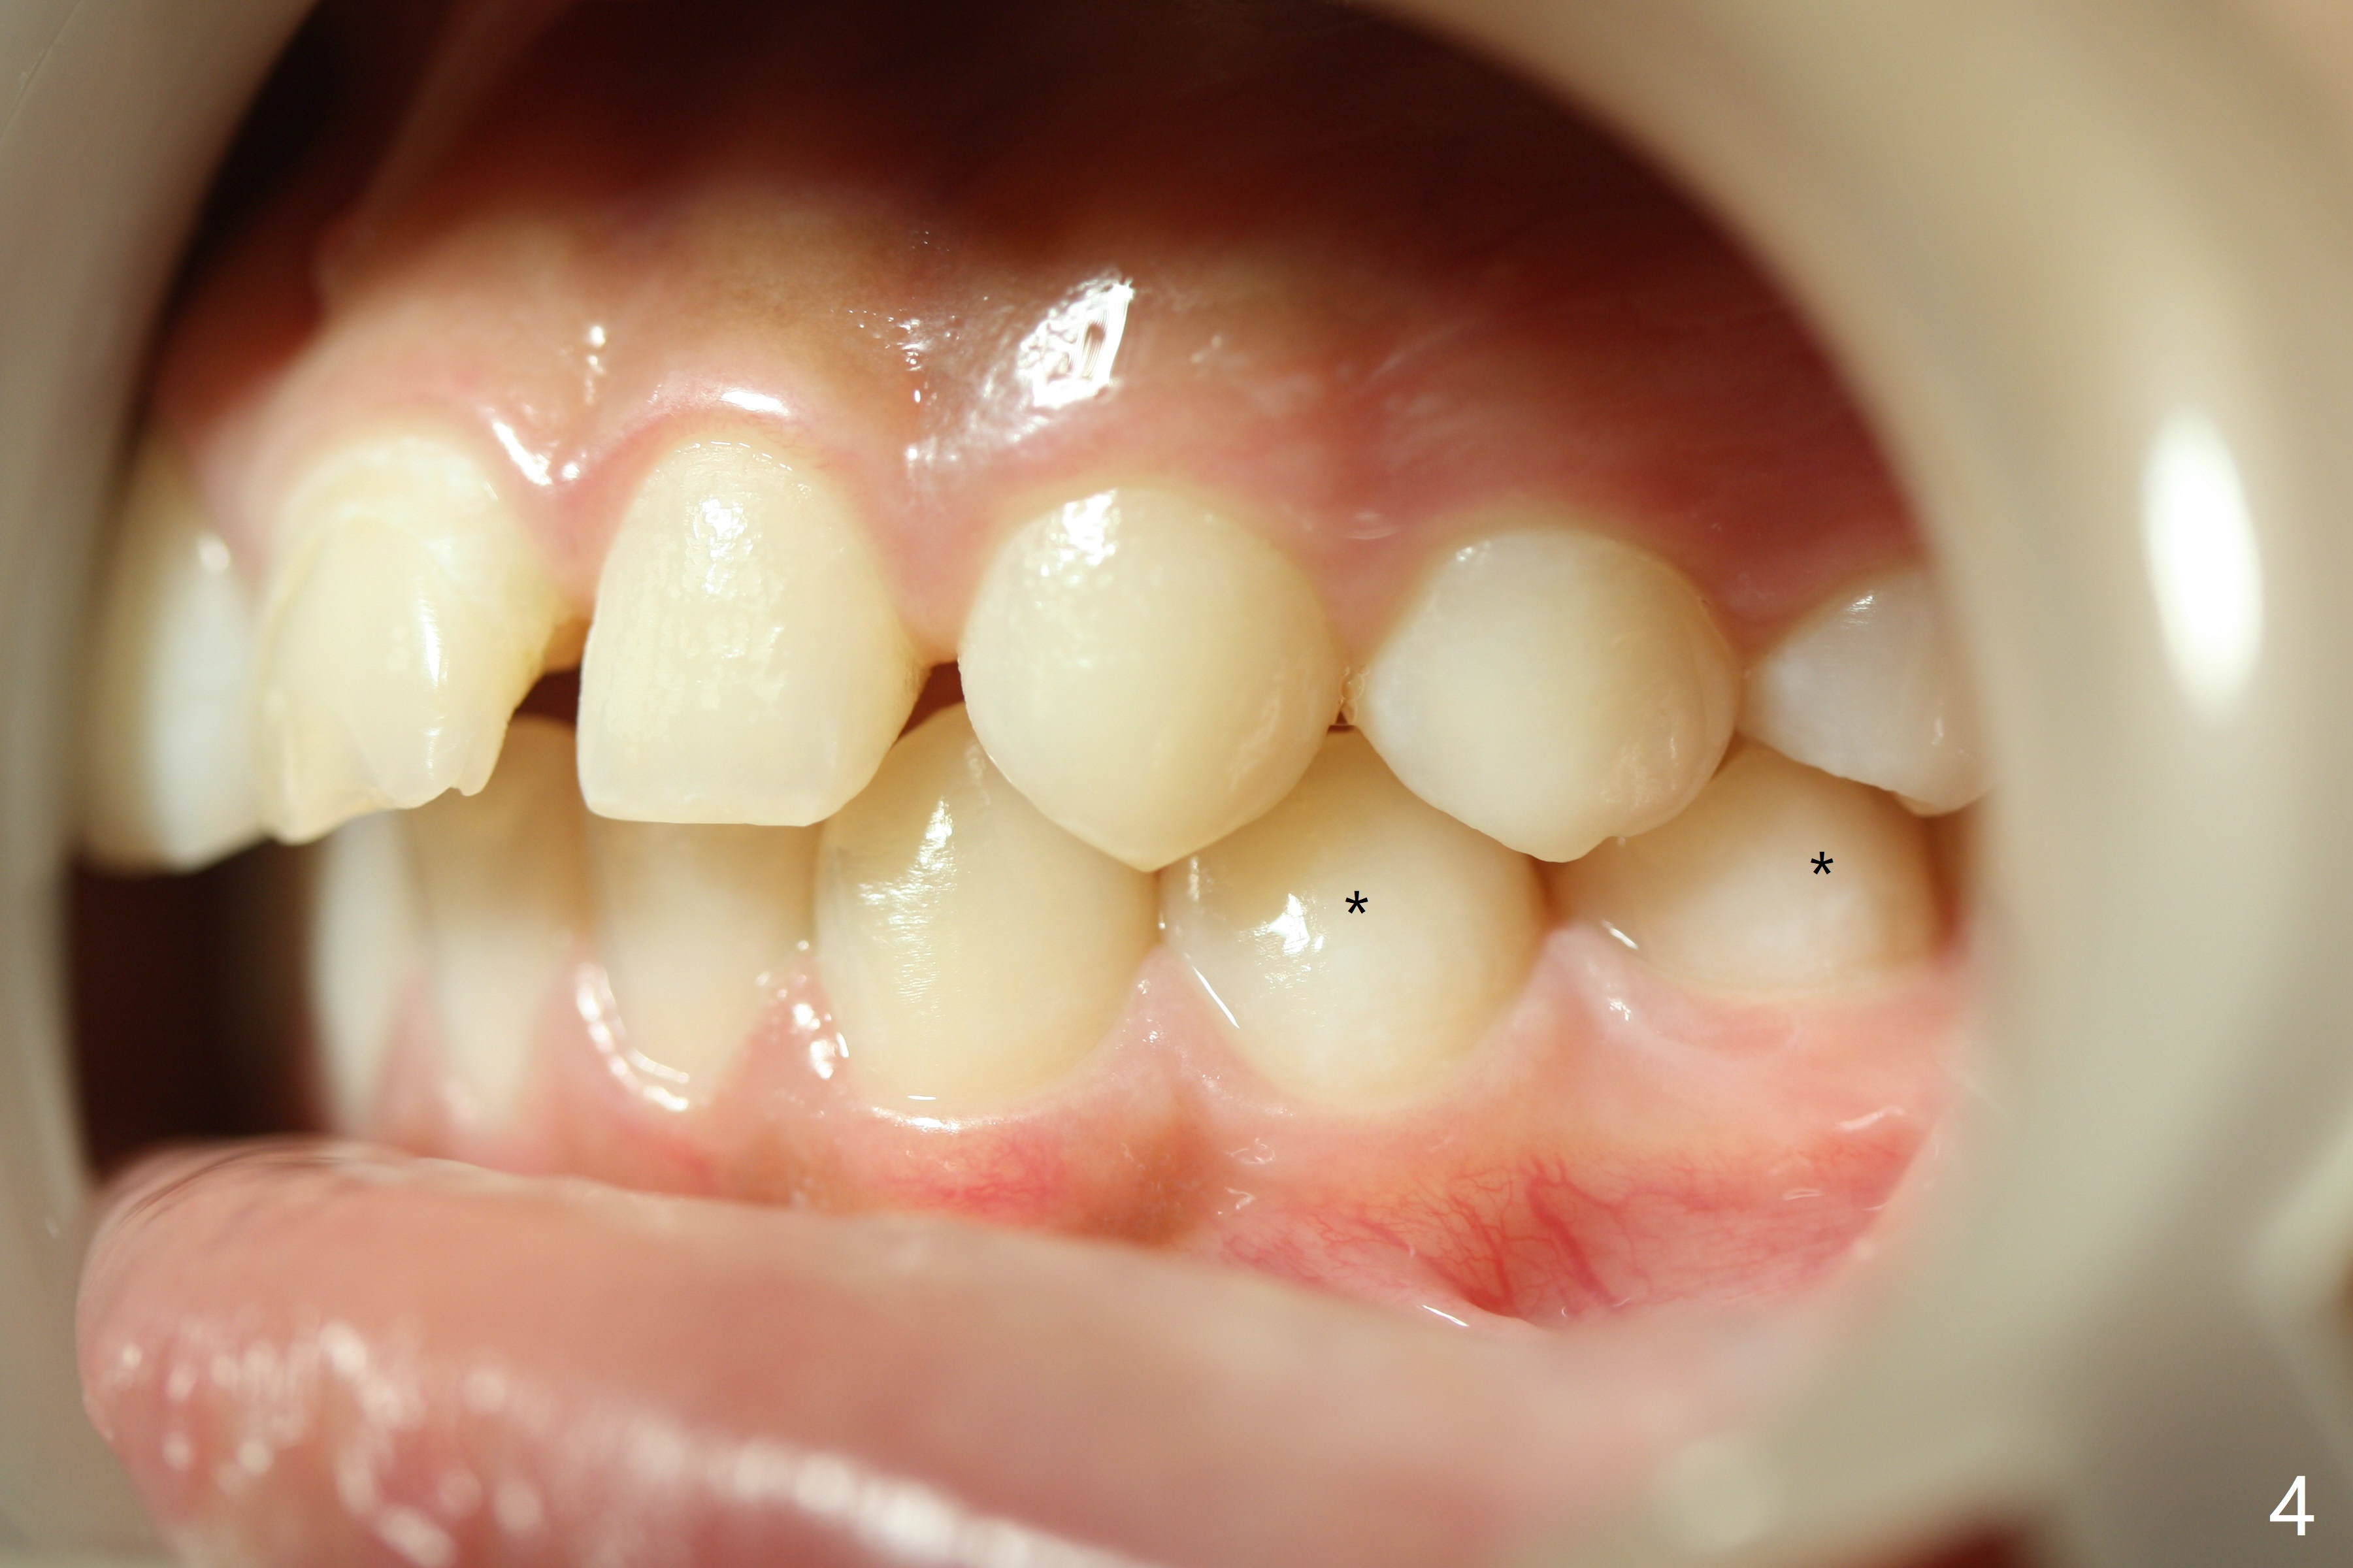

The lower right 2nd bicuspid of a 10-year-old woman seems to rotate before eruption (Fig.1: 5) and remains so when it erupts (Fig.2, at the age of 12).

LR5 rotation appears to be associated with poor interdigitation on the right side (Fig.3), as compared to the left (Fig.4). * in Fig.3-6 indicates height of contour of a lower bicuspid, where a bracket should be placed.